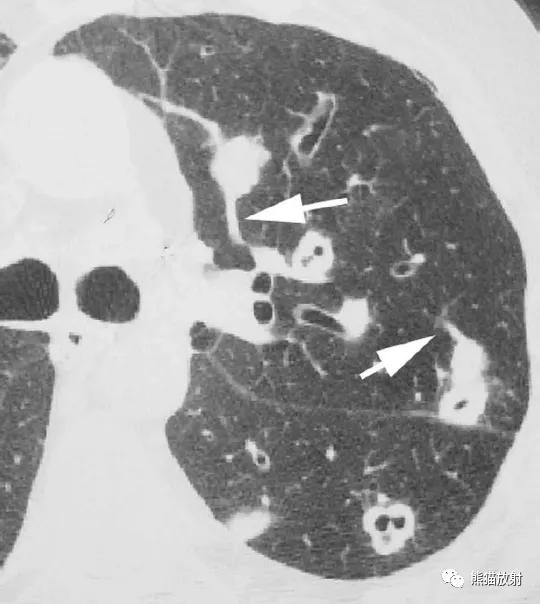

4、肺部的脓毒性栓子可来源于各种部位,包括心瓣膜(心内膜炎)、外周静脉(血栓性静脉炎)、静脉导管或起搏器电极线。

横断面CT图像上结节影常可见血管影与之相连(“供血血管征”)(图)。由于致病病原体的不同,结节常在不同的时期形成空洞,导致实性结节和结节伴大小不等的空洞同时存在。

↑ 脓毒性肺栓塞 Septic embolism

40岁男性,发热,静脉注射*品毒**史。CT显示左肺多发空洞性结节,不同的血管与结节相连。血培养金黄色葡萄球菌阳性。